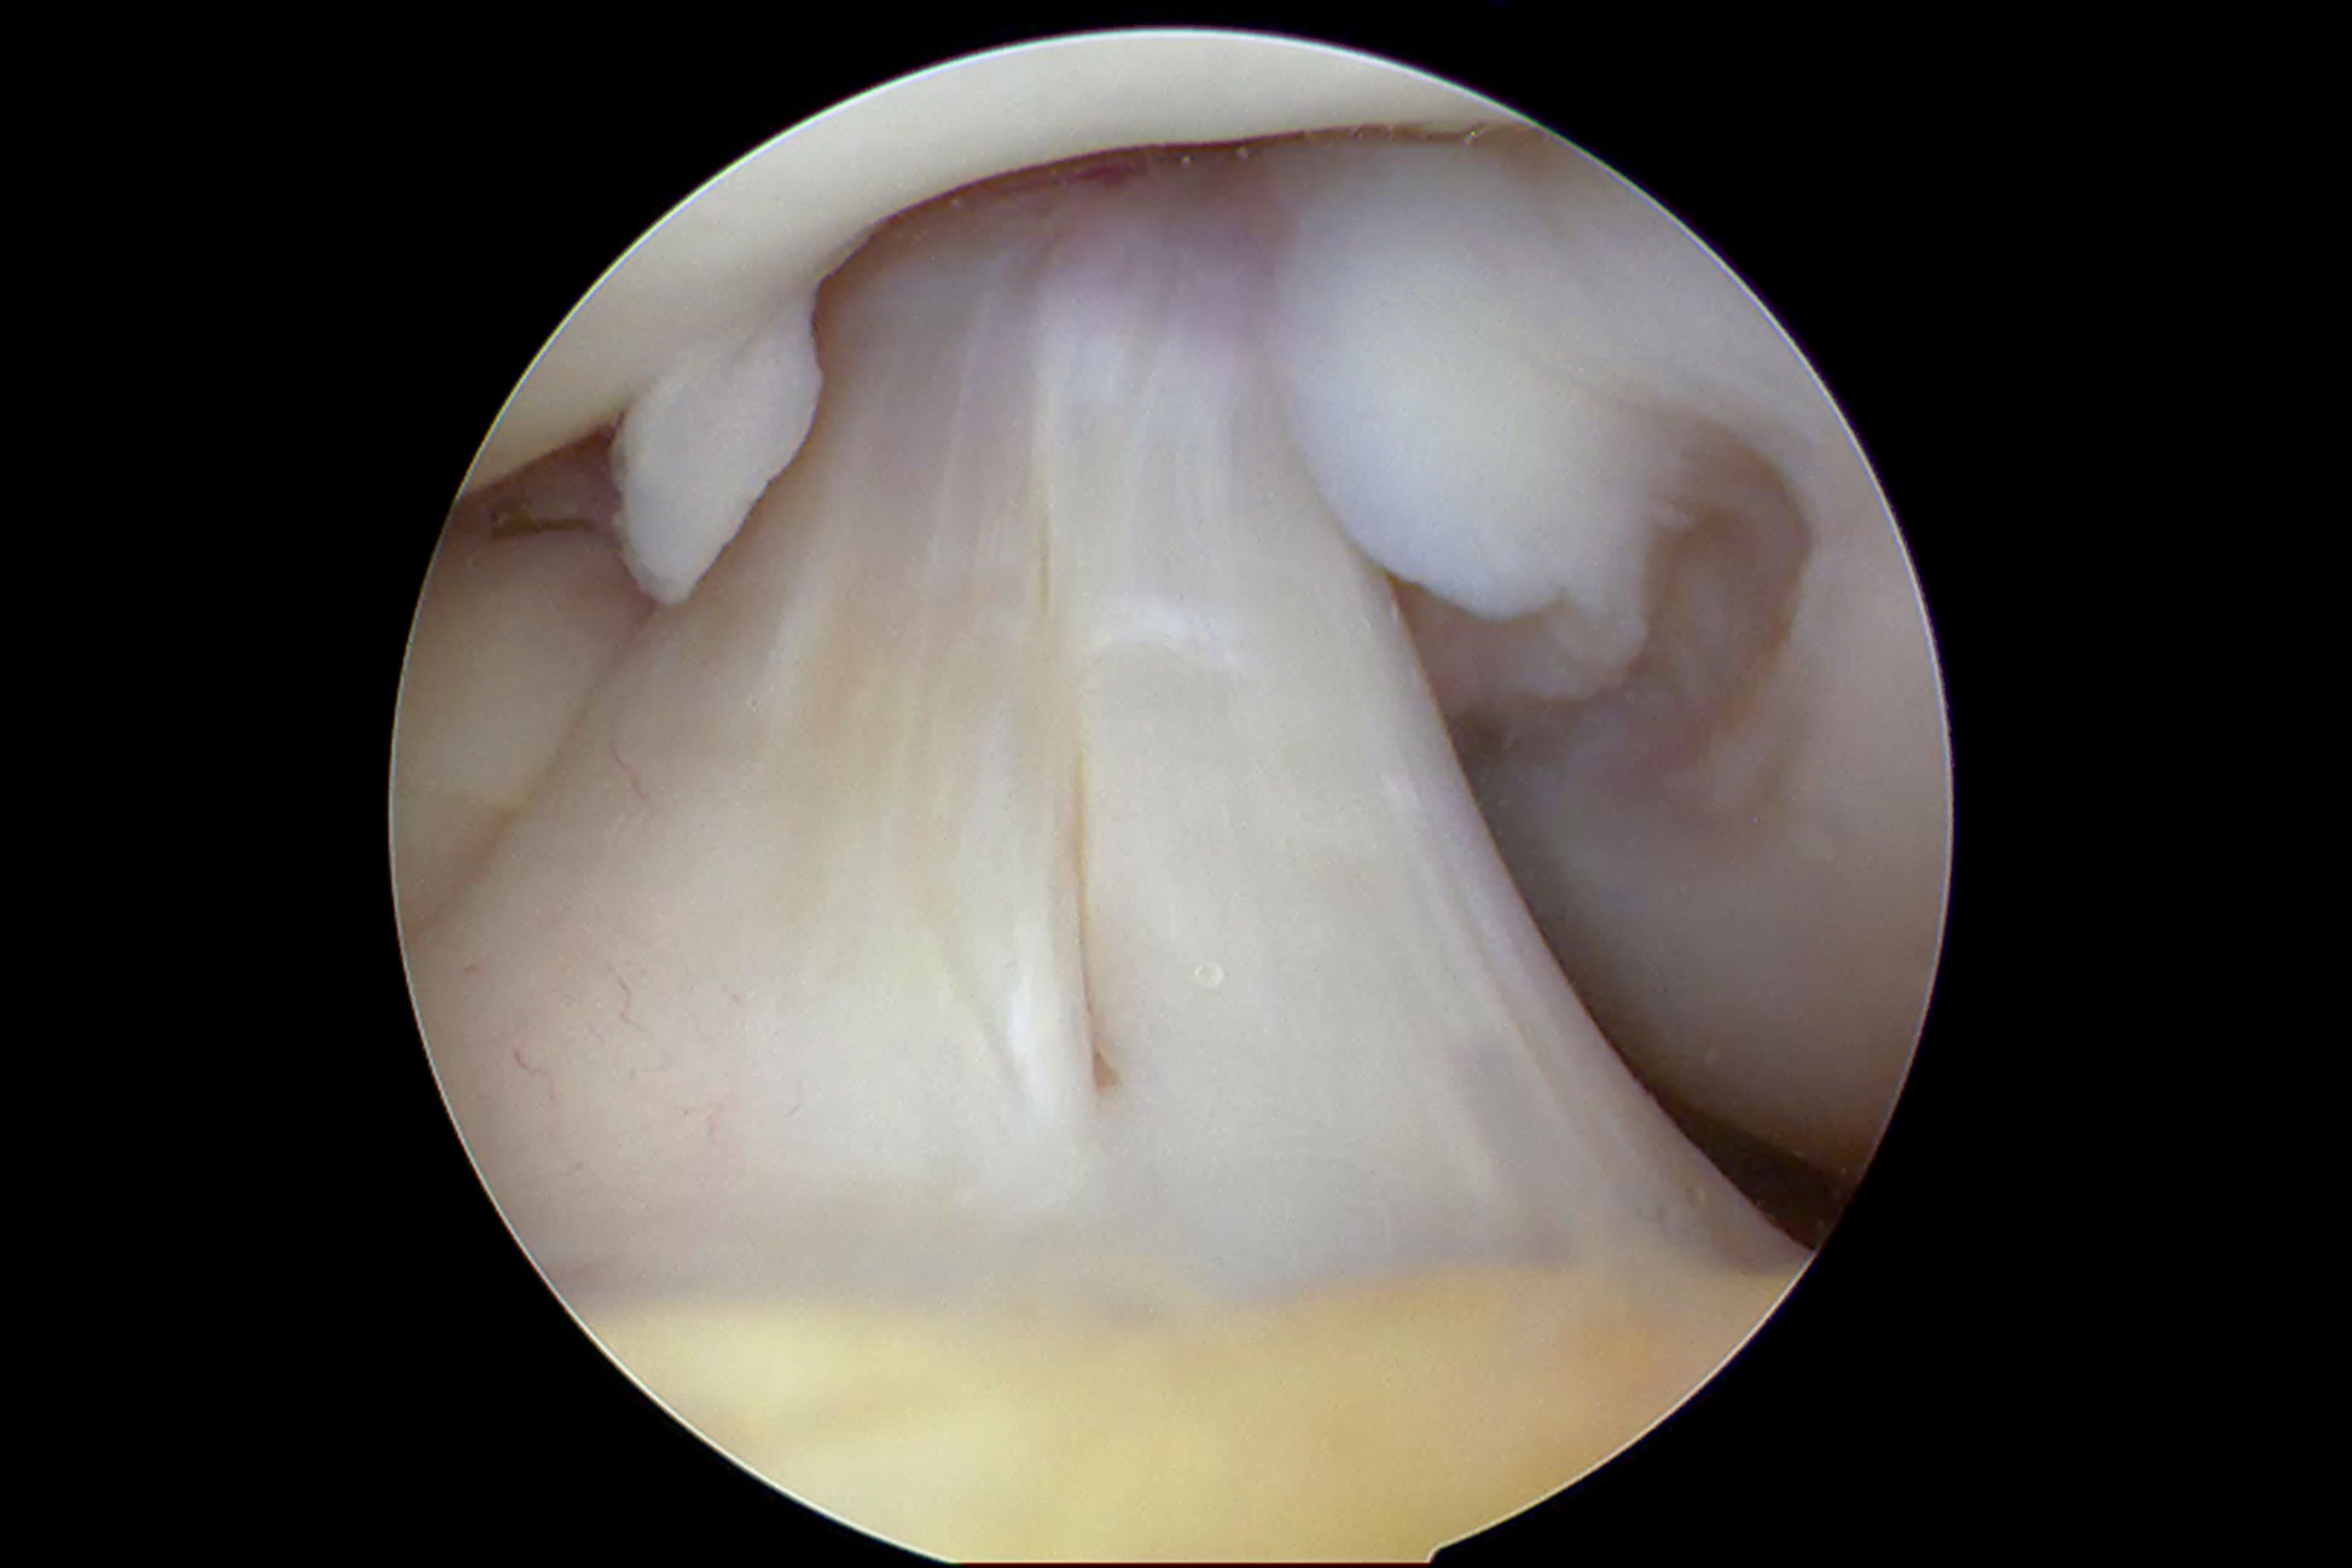

Bone grafting is typically performed under local or general anesthesia, depending on the complexity of the case. The surgeon will make an incision at the site where the graft is needed and then place the graft material. This material acts as a scaffold, encouraging new bone growth over time.